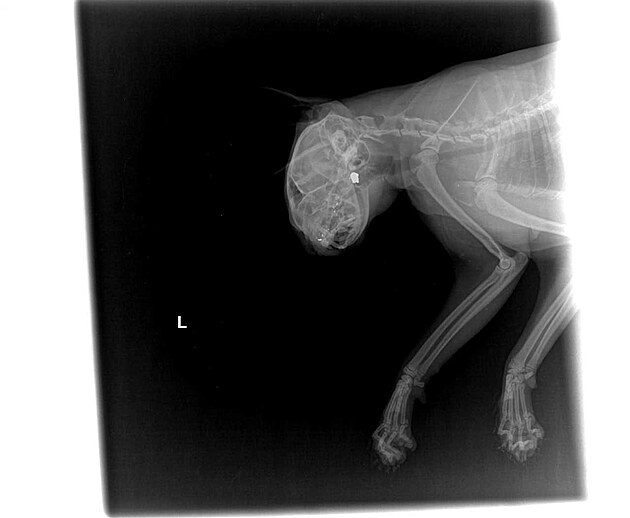

Zraněná kočka, kterou neznámý pachatel střelil ve Vícemilicích do hlavy. Zvíře utrpělo vážná poranění a hrozí mu trvalé oslepnutí.